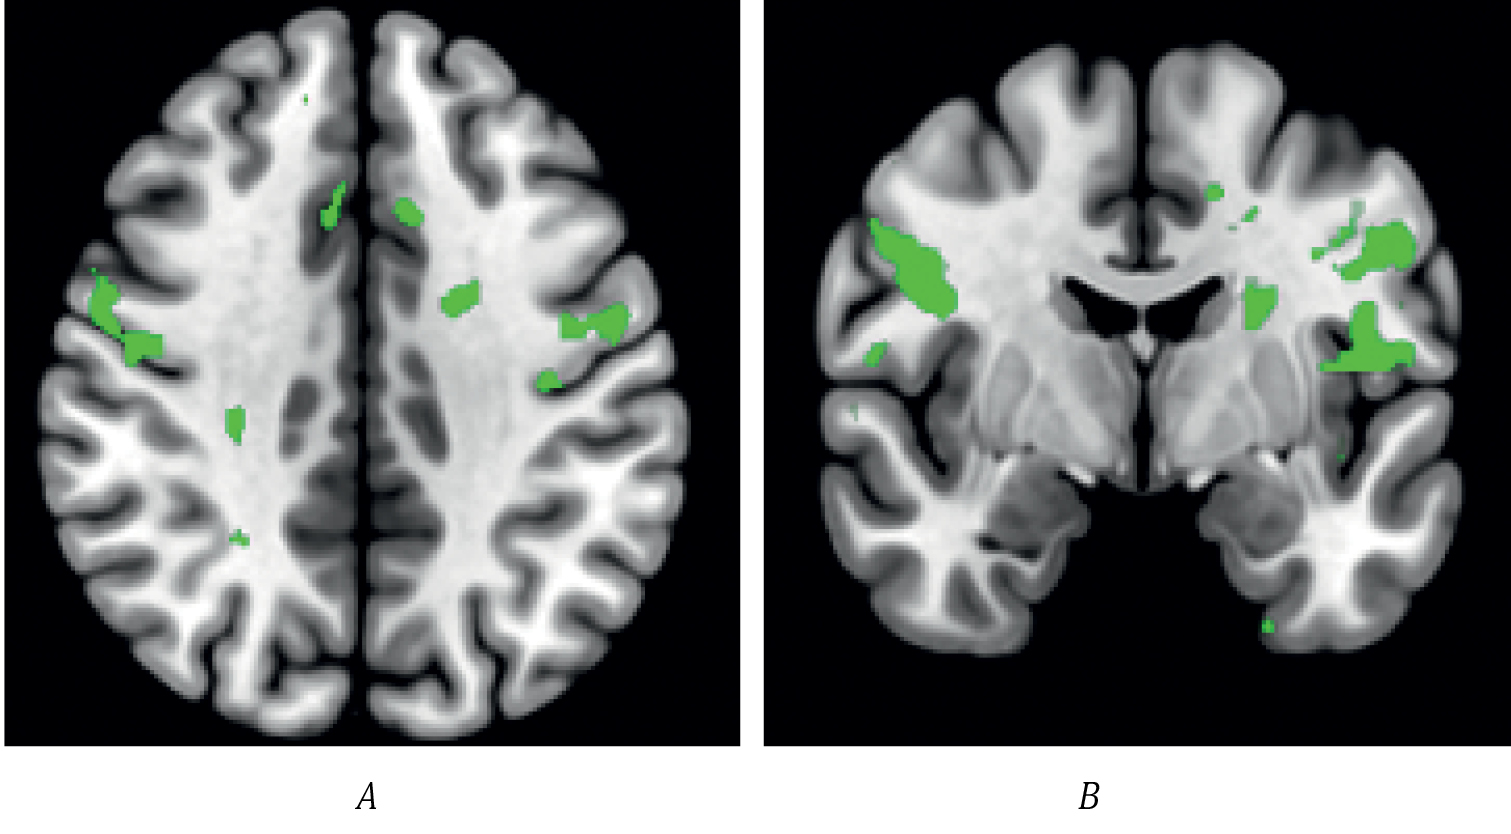

Сахарозаменители (аспартам, сукралоза, стевия, эритрит) предлагаются как более здоровая альтернатива сахарозе и фруктозе. Однако их влияние на мозговую активность и поведение человека остаётся предметом дискуссии. Некоторые исследования показывают, что сахарозаменители могут не активировать системы вознаграждения как углеводы, что может влиять на чувство насыщения и потребление пищи в дальнейшем. В контексте ожирения фМРТ используется для оценки функциональной нейрональной активности, участвующей в регуляции энергетического обмена и метаболизма. В Научном центре неврологии получены пилотные результаты сравнения эффектов сахарозы и сахарозаменителя с применением фМРТ, которые показали различия в активации в области дополнительной моторной и дорсолатеральной префронтальной коры среди здоровых добровольцев (рис. 2).

Рис. 2. Внутригрупповое сравнение активации головного мозга здоровых испытуемых при визуализации пищевой парадигмы (изображения аппетитной и неаппетитной еды) после приёма сахара и сахарозаменителя. На срезах головного мозга представлены зоны с отличающейся активацией. После приёма сахара отмечается бóльшая активация в дополнительной моторной и дорсолатеральной префронтальной коре с обеих сторон.

А — аксиальная проекция; В — коронарная проекция.